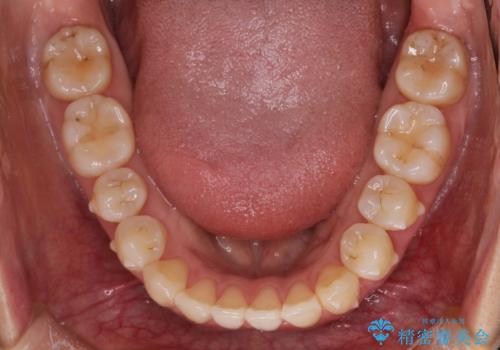

初診時の歯並びの状態としては、上下ともに前歯部に限局した軽度ののがたつき(叢生)がある状態でした。

主に歯列弓の拡大とディスキング(歯と歯の間に隙間を作る処置)を行い叢生を改善しました。

見た目、嚙み合わせ及び、治療期間や施術内容に大変ご満足いただきました。